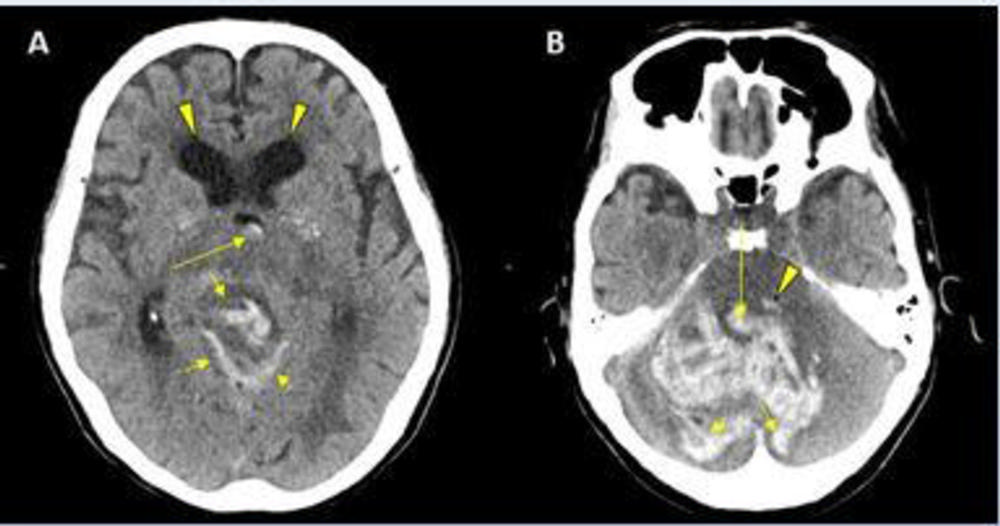

Figure 3. CT showing hemorrhage in a 68-year-old male patient with COVID-19 infection.